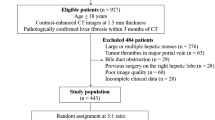

Fifteen studies [13, 26,27,28,29,30,31,32,33,34,35,36,37,38,39] were included that were published between 2018 and 2023 (Fig. 1). In these studies, radiomic analyses were performed involving 3718 patients with chronic liver diseases including hepatitis and MAFLD. The age of these patients was 47.3 years [95% confidence interval (CI): 42.0, 52.5]. The proportion of males was 69% [95% CI: 65, 73]. Histologically (biopsy/surgical) confirmed fibrosis stage was F0 in 13% [95% CI: 7,20], F1 in 17% [95% CI: 13, 23], F2 in 21% [95% CI: 17,26], F3 in 16% [95% CI: 13,19], and F4 in 27% [95% CI: 23, 33] of the patients. Radiological modalities used in these studies were: MRI (5), CT (3), ultrasonography (2), positron emission tomography (1), shear-wave elastography (2), and MRE (2).

Important characteristics of the included studies are given in Table S1. The quality of the included studies was moderate in general according to the QUADAS-2 scale (Table S2). The risk of bias was limited to the retrospective design of studies which could have introduced patient selection bias. Moreover, the interval between the index test and reference test was up to six months which might have impacted adequate flow and timing. Included studies also varied with regards to validation ranging from no validation [26], Five/Ten-fold cross-validation [27, 30, 32, 36, 39], and leave-one-out cross-validation [13] to internal validation [28, 30, 31, 33, 34, 37, 38], and internal and external validation [29]. There was no significant publication bias according to Egger’s test (Bias coefficient 0.114 [-11.80, 12.03]; p=0.984) or Begg’s test (Adjusted Kendall’s score -29±18; p=0.125) (Figure S1a and b).